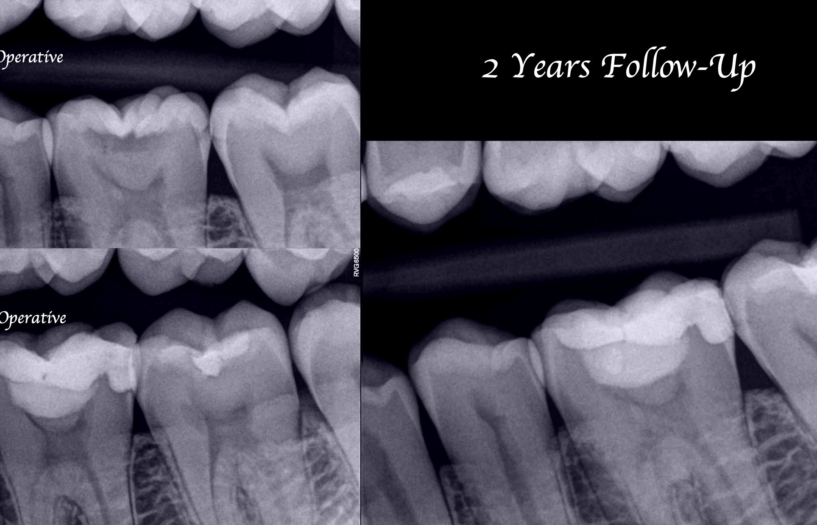

Calitatea restaurării definitive și adaptarea ei strânsă la structura dentinei pentru prevenirea infiltrărilor sunt factori cheie în succesul pe termen lung al procedurii. Adaptarea marginală corectă și continuitatea restaurării cu țesutul dentar pot fi observate în radiografia finală a procedurii (Fig. 8). S-a făcut o evaluare la șapte zile după tratament pentru a se asigura că pacienta este complet asimptomatică și aceasta a răspuns la testele de sensibilitate într-un mod normal. Un răspuns normal al țesuturilor a fost obținut în toate testele.

Una dintre principalele caracteristici ale Biodentine este manipularea ușoară, poate fi folosit ca substitut de dentină datorită rezistenței sale mari la compresie și oferă o bună aderență la structura dintelui. Caracteristicile sale înseamnă că este ușor de aplicat în regiunea de tratat și poate fi folosită ca bază pentru restaurarea coronară adezivă definitivă. Fig. 9 prezintă procedura de Terapie Pulpară Vitală. Sub formă radiografică, la controlul la doi ani, se poate observa retragerea cornului pulpar mezial. Unul dintre cele mai apreciate avantaje ale Biodentine este acela că nu pigmentează structura dintelui, făcându-l un material ideal pentru efectuarea coafajului în zona anterioră.

Fig. 2. Radiografia mușcăturii evidențiază o leziune carioasă a dintelui 19. Țesutul submineralizat este găsit în apropierea cornului pulpar mezial.

Fig. 8. Radiografia finală a procedurii de Terapie Pulpară Vitală. Se pot observa diferitele straturi de materiale utilizate, precum și adaptarea marginală corectă.

Fig. 9. Terapia Pulpară Vitală la dintele nr. 19 . La controlul la 2 ani se poate observa retragerea cornului pulpar mezial